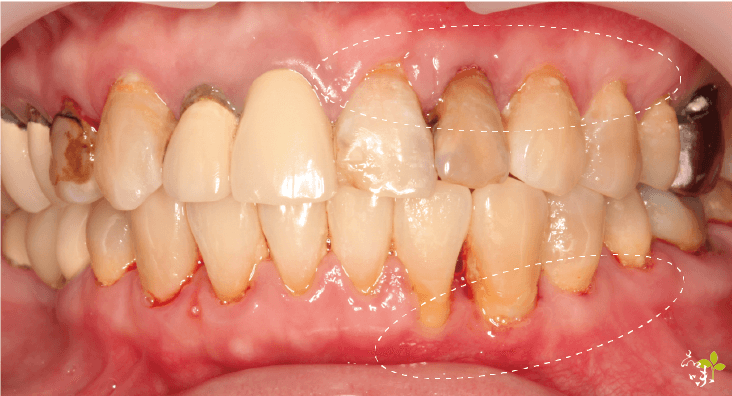

牙周病

牙周病會造成齒槽骨破壞,進而導致牙齦隨齒槽骨消失而後退,這時建議先進行牙周病治療才是上策。

而當牙齒已經出現鬆動或嚴重動搖的情形時,甚至是需要拔牙的情況,針孔微創牙齦手術是無效的。

牙齒縫、黑三角

牙齒縫中間未完全閉合所形成的三角形被稱為「黑三角」,這個問題目前並未有標準手術治療方式。如果你真的想改善牙縫和黑三角,可以考慮製作陶瓷貼片或牙齒矯正時磨掉些許表層齒質,藉由矯正將縫隙變小或關閉。